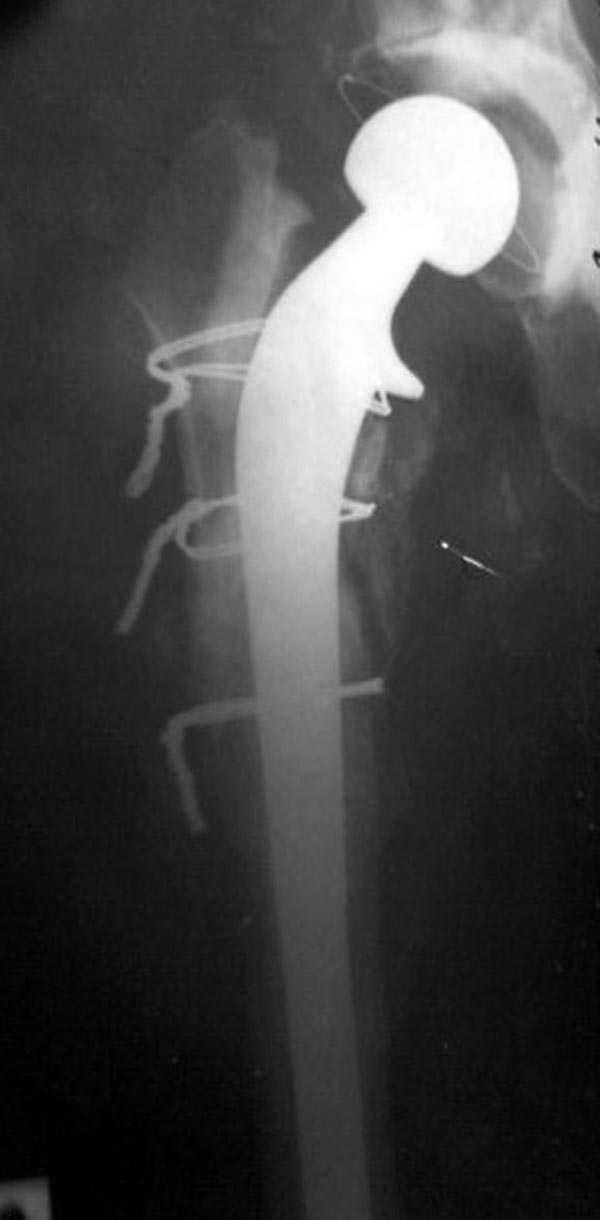

В дальнейшем заменил бы наружный фиксатор из частей аппарата Илизарова на более стабильный - стержневой фиксатор таз-бедро. В тазу можно применить полукольцо стержнями за крыло таза и дистально 2-3 стержня между передней и боковыми головками четерехглавой мышцы. Дельтовидная рама сверху вниз усилит конструкцию.

Можно на аппарате или на вытяжении немного дотянуть для создания запаса длины.

Следующий этап восстановление применением Blade Plate. Универсальный имплант и сегодня является уникальным по механическим характеристикам для восстановления проксимального отдела бедра где имеется сложная биомеханика.

Имеющиеся 130 градусные для вальгуса пластины от

Synthes короткие всего на две дырки, выход, обычная длинная 95 градусная Blade Plate разгибается до 105-110 градусов. Металл трудно поддается деформации, и его не согнуть между тепловой батереей в операционной, надо подготовить заранее после предварительного нагрева в механической мастерской.

Проведя клинок горизонтально в шейку, и соединив с

диафизом бедра создаем небольшой вальгус, тем самым увеличиваем длину конечности. Образовавшийся дефект кости надо заполнить блоком цемента, который предупреждает инфицирования и дает устойчивость конструкции. После затихания процесса можно приступить ко вторичному заполнению аутокостью или можно применить костную массу из того же местного костного регенерата.

Обещанный Synthesом локинг вариант пластины еще до нас не дошел, но блокирующая на пластине шайба поможет созданию локинг концепт.